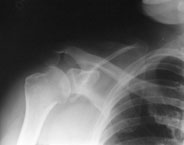

Ein 44-jähriger Patient ist auf dem ersten Eis des Winters ausgerutscht und auf die rechte Schulter gestürzt.

Er klagt über starke Schmerzen im Bereich der rechten Schulter und ein Instabilitätsgefühl im Gelenk. Die Beweglichkeit des Arms ist aufgrund der Schmerzen eingeschränkt, Durchlutung und Sensibilität sind normal.

linke Schulter tangential

Welche Befunde liegen vor (mehrere richtige Antworten möglich)?